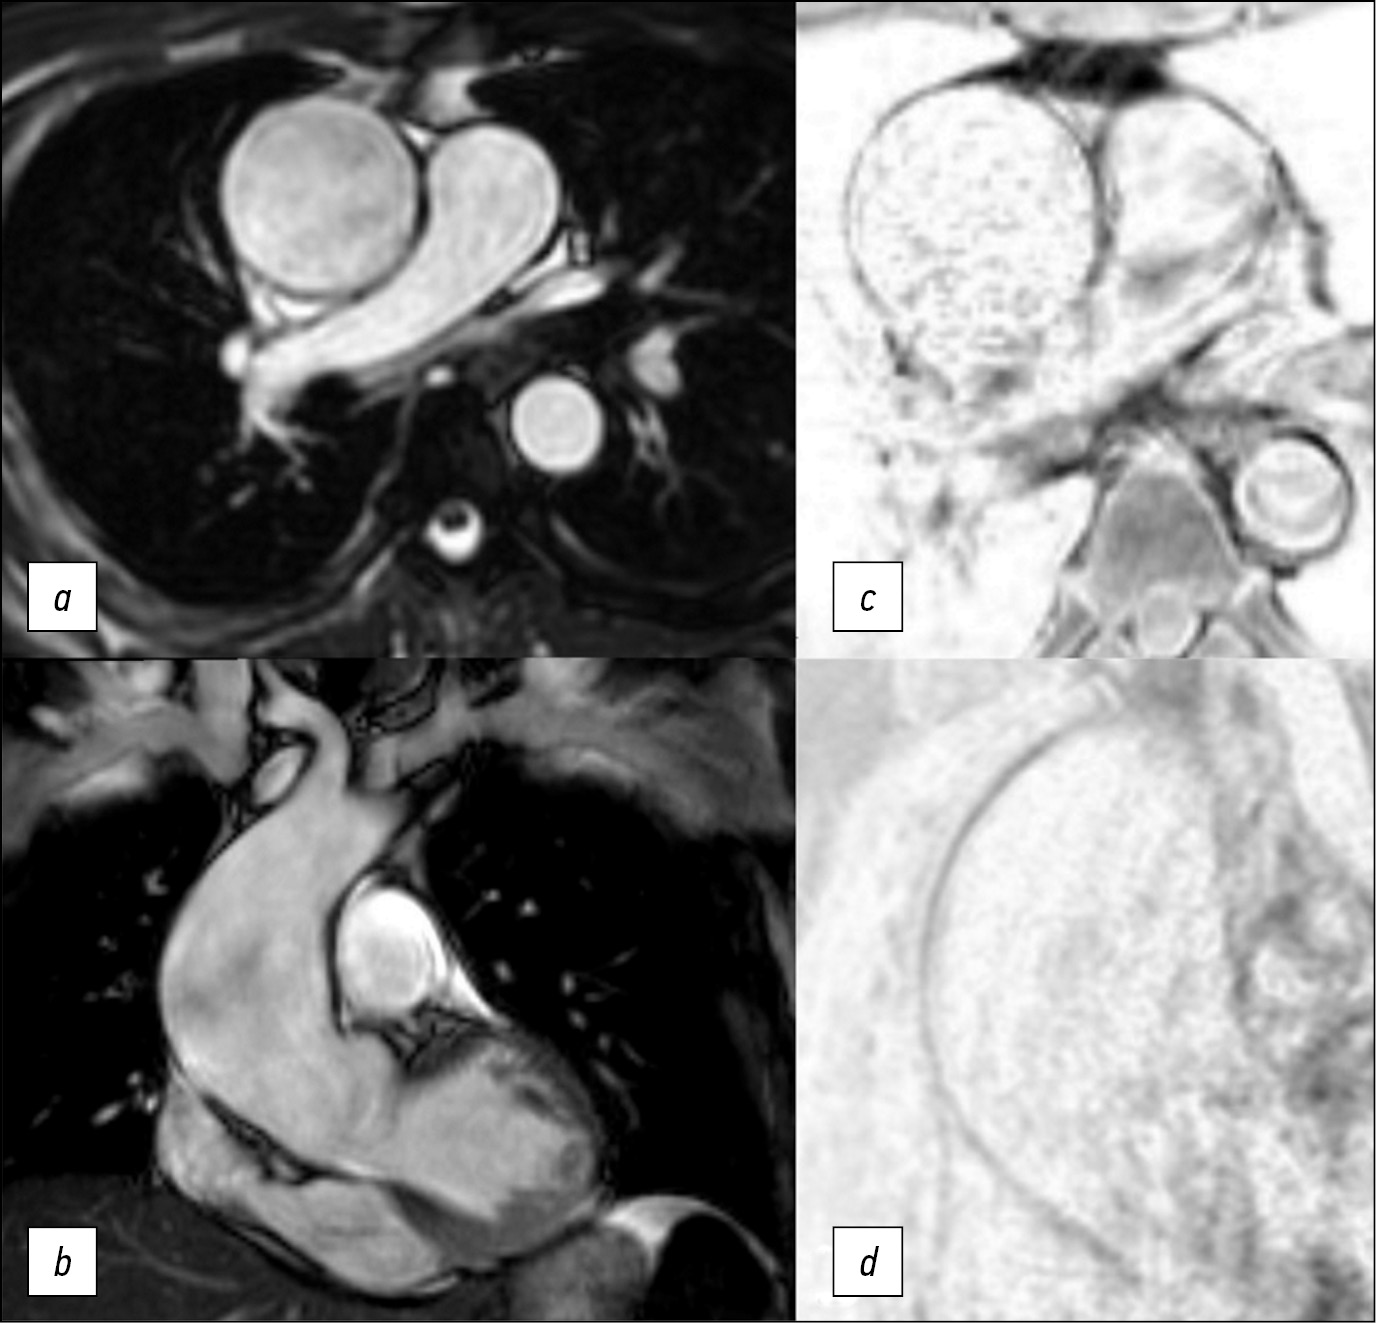

Optimized biparametric magnetic resonance imaging protocol for prostate cancer detection

Аннотация

BACKGROUND: Prostate cancer is one of the most commonly diagnosed cancers in men worldwide. PI-RADS v2.1 contains the requirements for the magnetic resonance imaging protocol, which cannot be fully implemented on a significant component of functioning scanners. Consequently, magnetic resonance imaging approaches vary in different medical organizations and often do not allow for a qualitative interpretation of images and diagnosis of the target pathology.

AIM: To develop a biparametric magnetic resonance imaging protocol optimized for the existing magnetic resonance imaging scanners for the diagnosis of prostate cancer and to allow the screening and detection of neoplasms as early as possible. Simultaneously, the protocol should fulfill the current PI-RADS v2.1 recommendations to the maximum possible extent and meet the requirements of effective workflow in the radiology department.

MATERIALS AND METHODS: Preliminary analysis of prostate magnetic resonance imaging scanning in medical organizations of the Moscow Health Care Department showed the absence of a unified approach. Using the iterative adjustment of scanning parameters, we adjusted the protocol to ensure acceptable quality with maximum available compliance with PI-RADS v2.1.

To quantify the quality of the images, we used the magnetic resonance imaging phantom recommended by the American College of Radiology.

RESULTS: The biparametric protocol was developed for Excelart Vantage 1.5 T, including T2-weighted images in three planes and diffusion-weighted images, which took less than 11 min. Moreover, the image quality parameters (intensity inhomogeneity, nonlinearity, resolution, and slice thickness) were within the acceptable ranges recommended by the magnetic resonance imaging manufacturer.

CONCLUSION: The prostate may be effectively evaluated using the proposed magnetic resonance imaging protocol. Introducing it into practice could have a significant impact on the detection of prostate cancer in men. The entire duration of the protocol provides a possibility to supplement it with any sequences, depending on the final purpose of investigation.